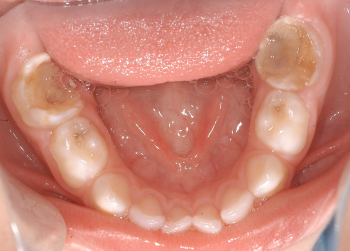

Odontopediatría

Caso 1